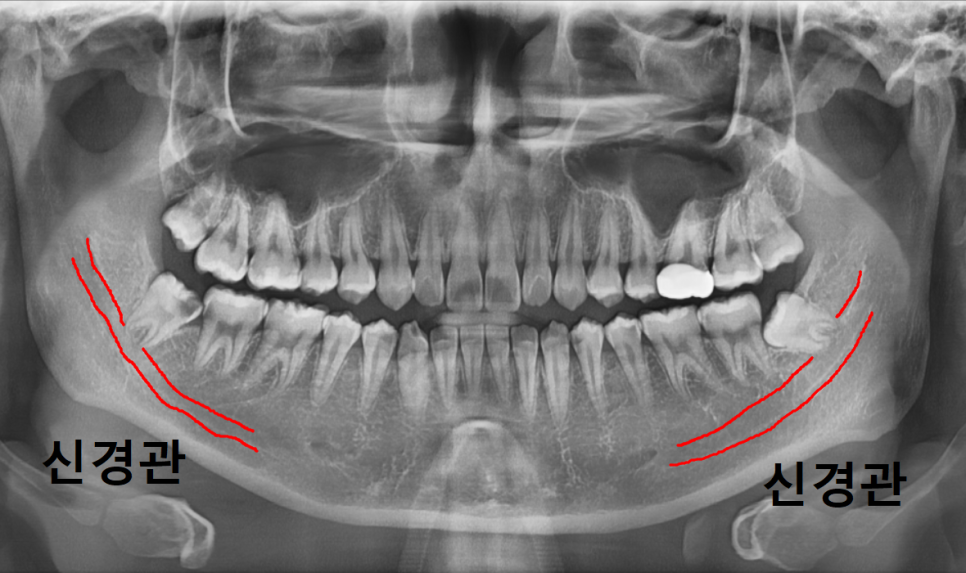

또한 양쪽 아래 사랑니 모두

엑스레이상에서 아래턱 신경관과 겹쳐 보였습니다.

240919

이 경우에는 단순 엑스레이만으로는

신경과의 거리를 정확히 판단하기 어렵기 때문에

보다 안전한 발치를 위해 CT 촬영을 진행했습니다.

240920 상일동 사랑니 매복 방치

CT로 확인해 보니

신경관과 사랑니 뿌리가 매우 근접해 있어

발치 시 각별한 주의가 필요한 상황이었습니다.

240920